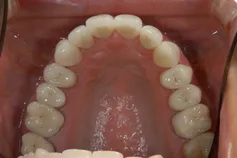

[症例2]

治療前は臼歯部は保険の冠のため金属色が目立ちます。上顎の前歯はセラミックですが、古いタイプの治療法ため裏側に金属が露出しています。

矯正治療後に部分被せも含めて全てセラミックで治療しました。

右下6番は歯を真ん中で分割して2本の冠が入っていましたが、抜歯してインプラントが入っています。

上下顎とも金属色の見えない美しい歯並びになりました。

- 治療期間:約1年

- 治療費:240万円

- 治療回数:26回